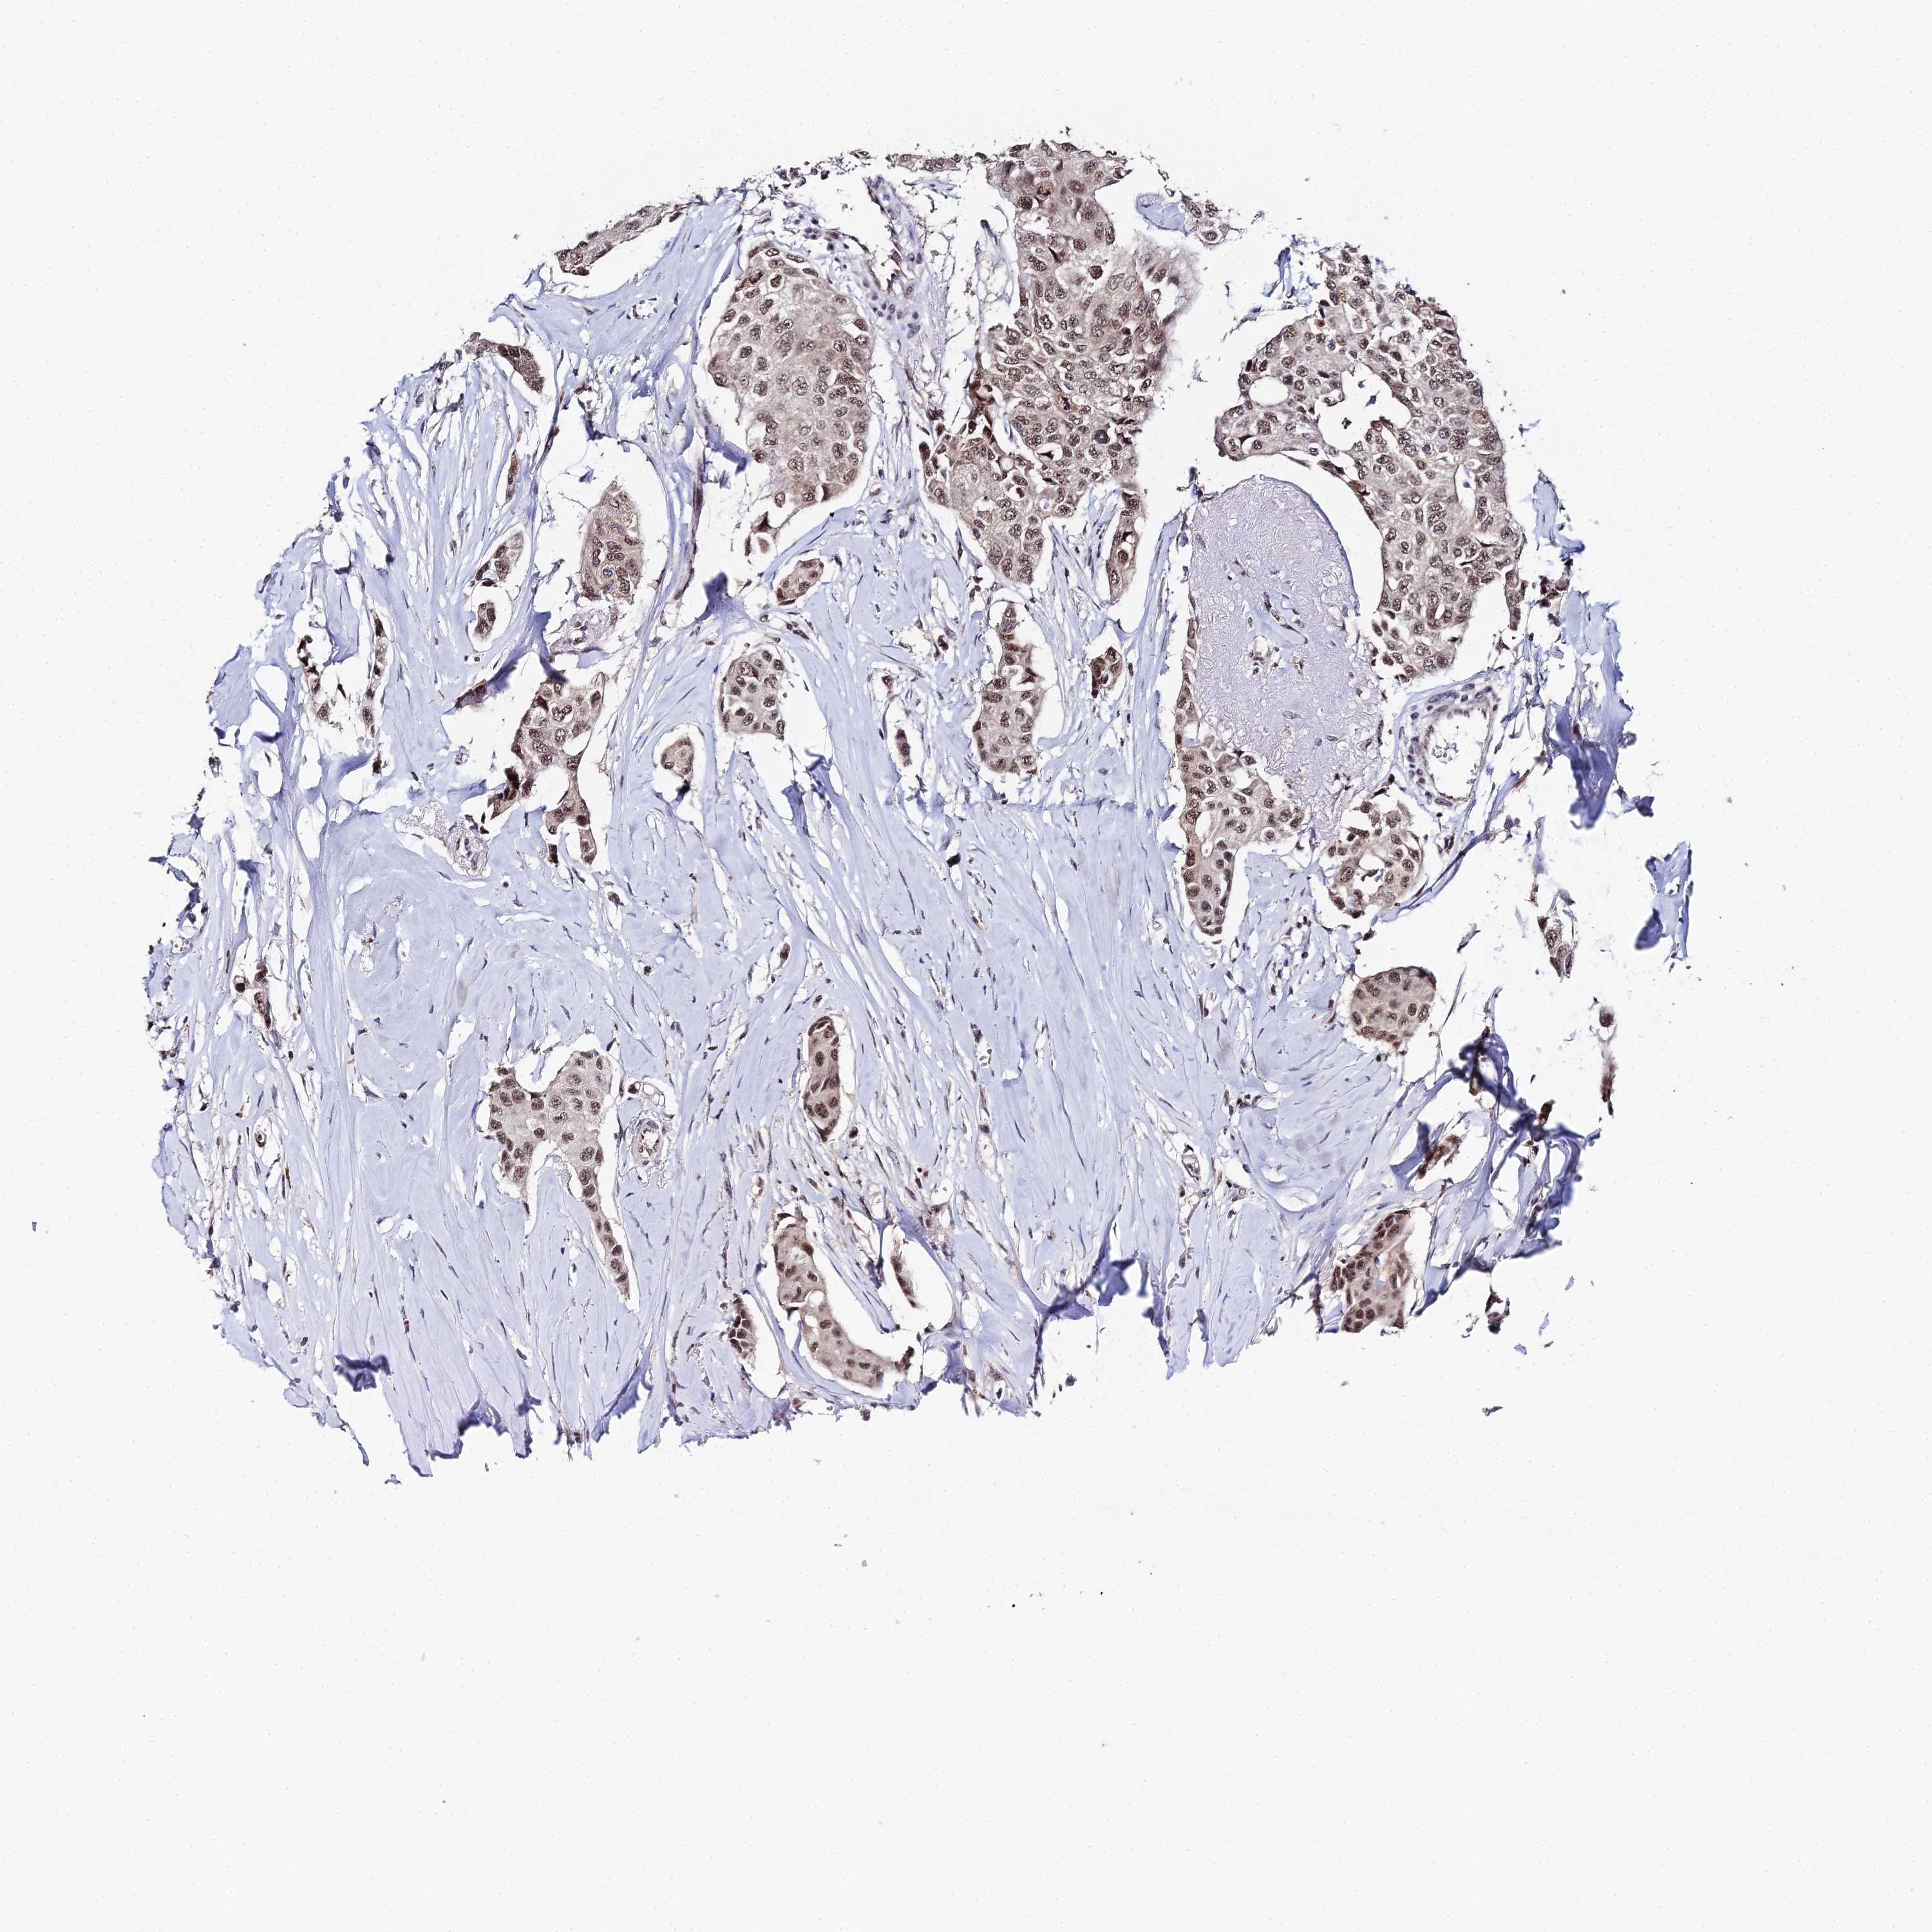

CANCER BREAST CANCER Show tissue menu

BRCA TCGA BRCA VALIDATION PROTEIN EXPRESSION